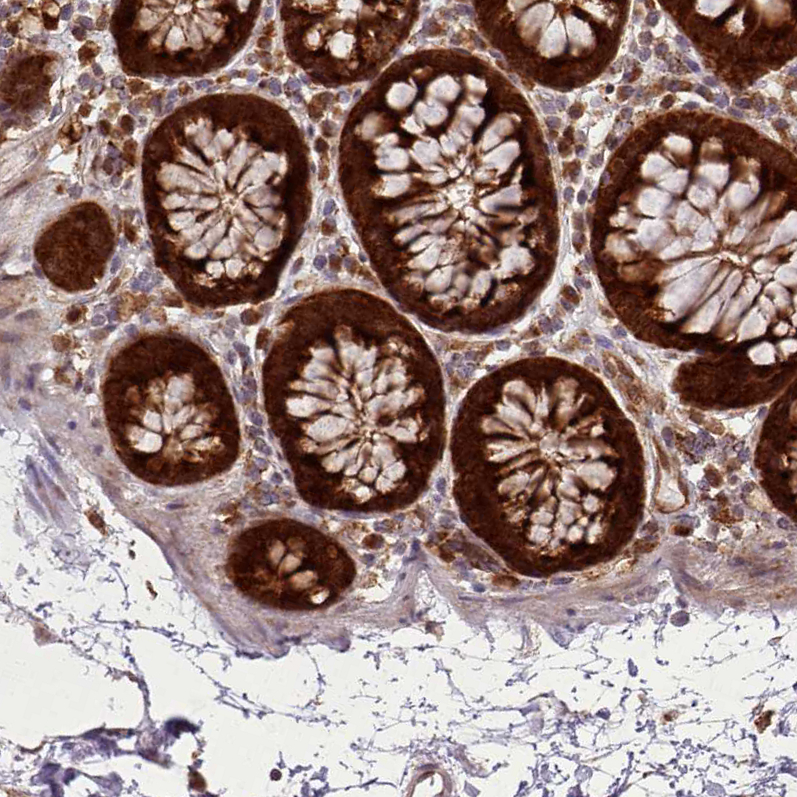

Immunohistochemical staining of human colon shows moderate to strong cytoplasmic positivity in glandular cells.